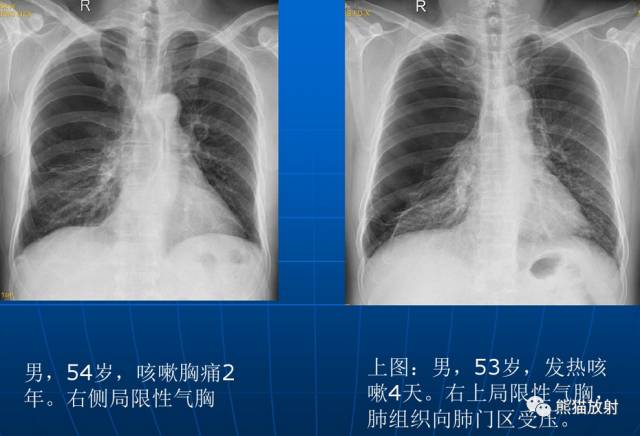

局限性阻塞性肺气肿是由于一个较大的支气管产生部分性阻塞所引起。该病可见于支气管内异物、小儿急性肺炎、早期支气管肿瘤和支气管慢性炎性狭窄包括结核等病史。

X线表现:在肺野内有局部的透亮度增高区域,其部位和范围取决于支气管部分阻塞的所在。至于有无胸廓、横膈等改变取决于病变的范围和部位。

| 局限性阻塞性肺气肿 |